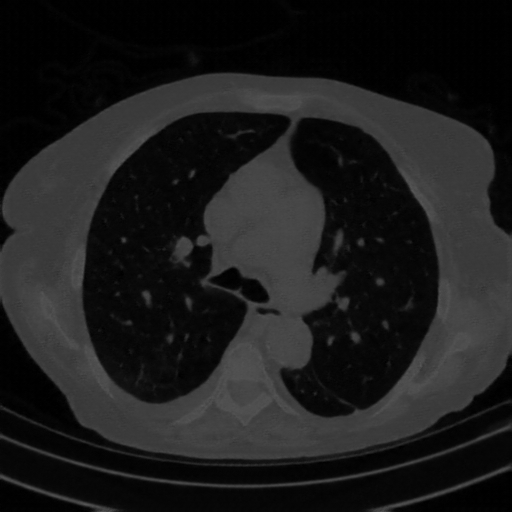

4Γ—3 grid: Rows show different image types (Original NATIVE, Reconstructed NATIVE, Original VENOUS, Generated VENOUS), Columns show windowing techniques (No Window, Lung Window, Mediastinum Window)

Original VENOUS CT scan

Lung window (WL -600, WW 1500 β†’ Low βˆ’1350, High +150)

Generated VENOUS CT scan (A→B translation)